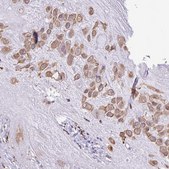

HPA053149

Anti-SGPP1 antibody produced in rabbit

IHC

immunohistochemistry: 1:200-1:500

All Prestige Antibodies Powered by Atlas Antibodies are developed and validated by the Human Protein Atlas (HPA) project and as a result, are supported by the most extensive characterization in the industry.

The Human Protein Atlas project can be subdivided into three efforts: Human Tissue Atlas, Cancer Atlas, and Human Cell Atlas. The antibodies that have been generated in support of the Tissue and Cancer Atlas projects have been tested by immunohistochemistry against hundreds of normal and disease tissues and through the recent efforts of the Human Cell Atlas project, many have been characterized by immunofluorescence to map the human proteome not only at the tissue level but now at the subcellular level. These images and the collection of this vast data set can be viewed on the Human Protein Atlas (HPA) site by clicking on the Image Gallery link. We also provide Prestige Antibodies® protocols and other useful information.

• IHC tissue array of 44 normal human tissues and 20 of the most common cancer type tissues.